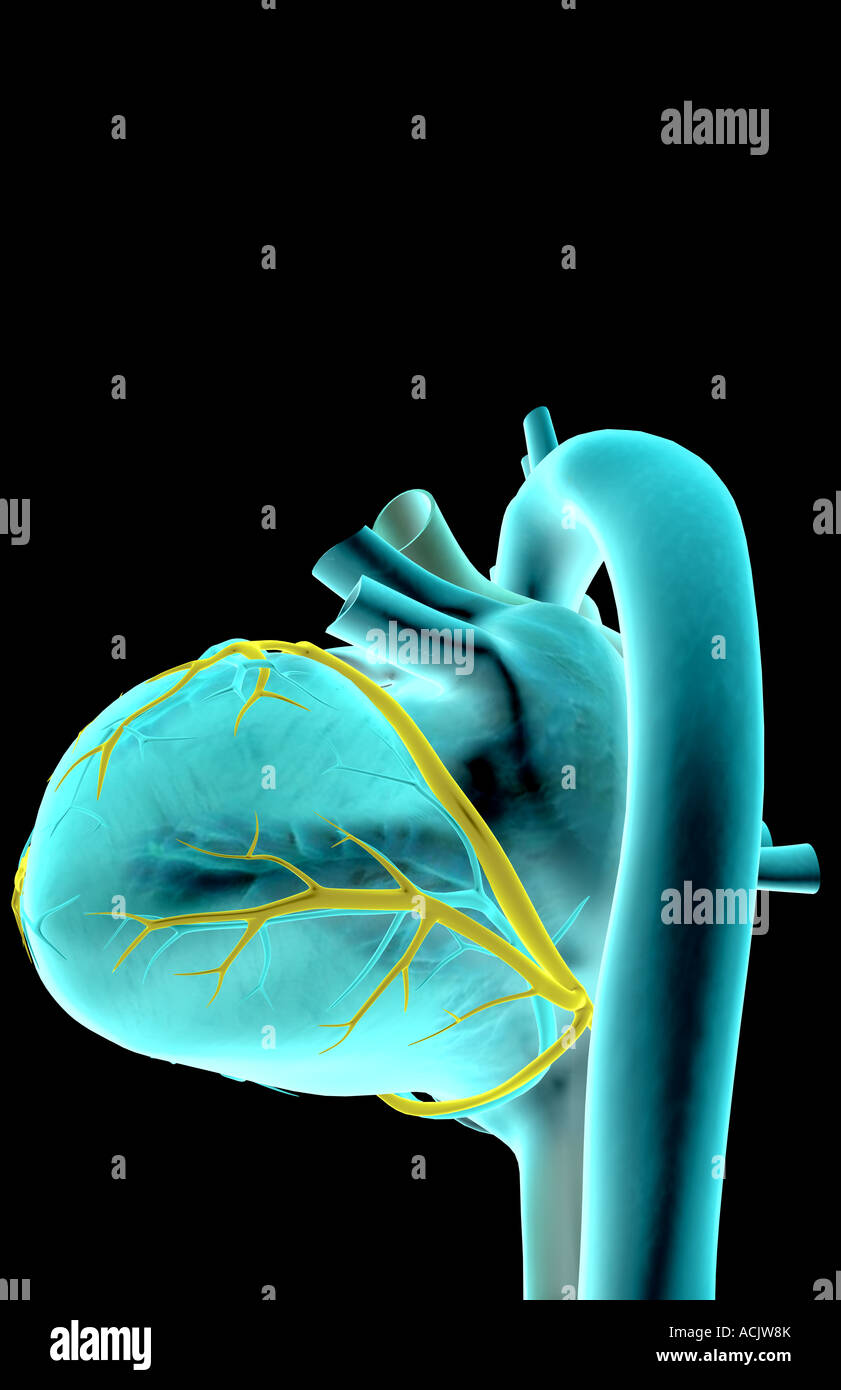

The coronary vessels of the heart Stock Photohttps://www.alamy.com/image-license-details/?v=1https://www.alamy.com/stock-photo-the-coronary-vessels-of-the-heart-13173426.html

The coronary vessels of the heart Stock Photohttps://www.alamy.com/image-license-details/?v=1https://www.alamy.com/stock-photo-the-coronary-vessels-of-the-heart-13173426.htmlRFACJW8K–The coronary vessels of the heart